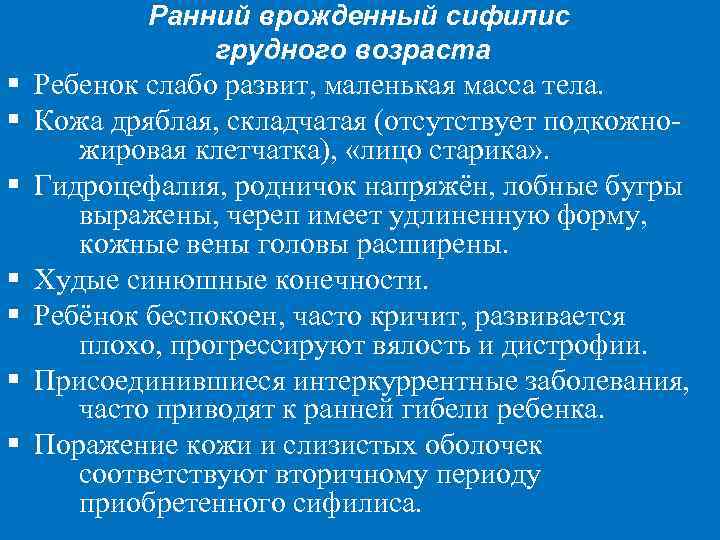

Ранний врожденный сифилис грудного возраста § Ребенок слабо развит, маленькая масса тела. § Кожа дряблая, складчатая (отсутствует подкожножировая клетчатка), «лицо старика» . § Гидроцефалия, родничок напряжён, лобные бугры выражены, череп имеет удлиненную форму, кожные вены головы расширены. § Худые синюшные конечности. § Ребёнок беспокоен, часто кричит, развивается плохо, прогрессируют вялость и дистрофии. § Присоединившиеся интеркуррентные заболевания, часто приводят к ранней гибели ребенка. § Поражение кожи и слизистых оболочек соответствуют вторичному периоду приобретенного сифилиса.

Ранний врожденный сифилис «лицо старика»